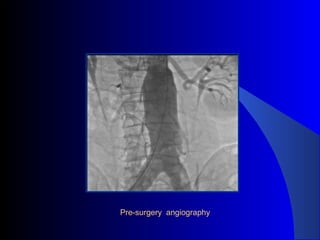

The document discusses the clinical application of the Endurant stent graft system in treating aorto-bisiliac aneurysms, detailing procedures performed on two male patients aged 72 and 73. Each patient had a history of dyslipidemia and carotid atherosclerosis, with procedures involving the bilateral bell bottom technique and the use of coils and fibrin glue. It includes pre-surgery imaging, intrasurgery angiography, and follow-up control scans to monitor outcomes.